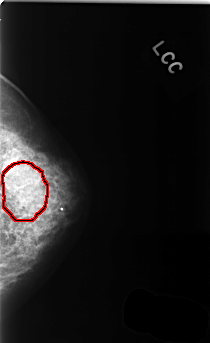

C_0368_1.LEFT_CC

LEFT_CC LINES 4456 PIXELS_PER_LINE 2720 BITS_PER_PIXEL 12 RESOLUTION 50 OVERLAY

FILE: C_0368_1.LEFT_CC.OVERLAY

TOTAL_ABNORMALITIES 1

ABNORMALITY 1

LESION_TYPE CALCIFICATION TYPE AMORPHOUS DISTRIBUTION SEGMENTAL

ASSESSMENT 4

SUBTLETY 2

PATHOLOGY BENIGN

TOTAL_OUTLINES 1

BOUNDARY